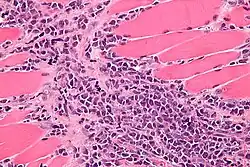

| Micrograph of a myeloid sarcoma within muscle. H&E stain. | |

A myeloid sarcoma (chloroma, granulocytic sarcoma,[1]: 744 extramedullary myeloid tumor) is a solid tumor composed of immature white blood cells[2] called myeloblasts. A chloroma is an extramedullary manifestation of acute myeloid leukemia; in other words, it is a solid collection of leukemic cells occurring outside of the bone marrow.